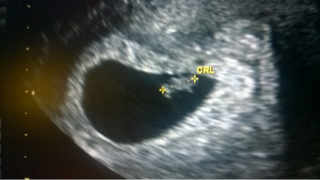

Moikka tytöt, paineet kasvoivat täällä liian koviksi ja menetin yöunet tämän asian kanssa. Miehenikään ei saanut unta, joten hän oli etsinyt minulle täksi päiväksi lääkärin ja ar-ultran. Sieltä äsken tultiin. Mitaksi tuli 6+4 ja "kädet" hänellä on sekä se syke:

ImageUploadedByVau Foorumi1459336351.251662.jpg

Katjusha rv. 6+6 ja seuraava lääkärinaika 5.4.